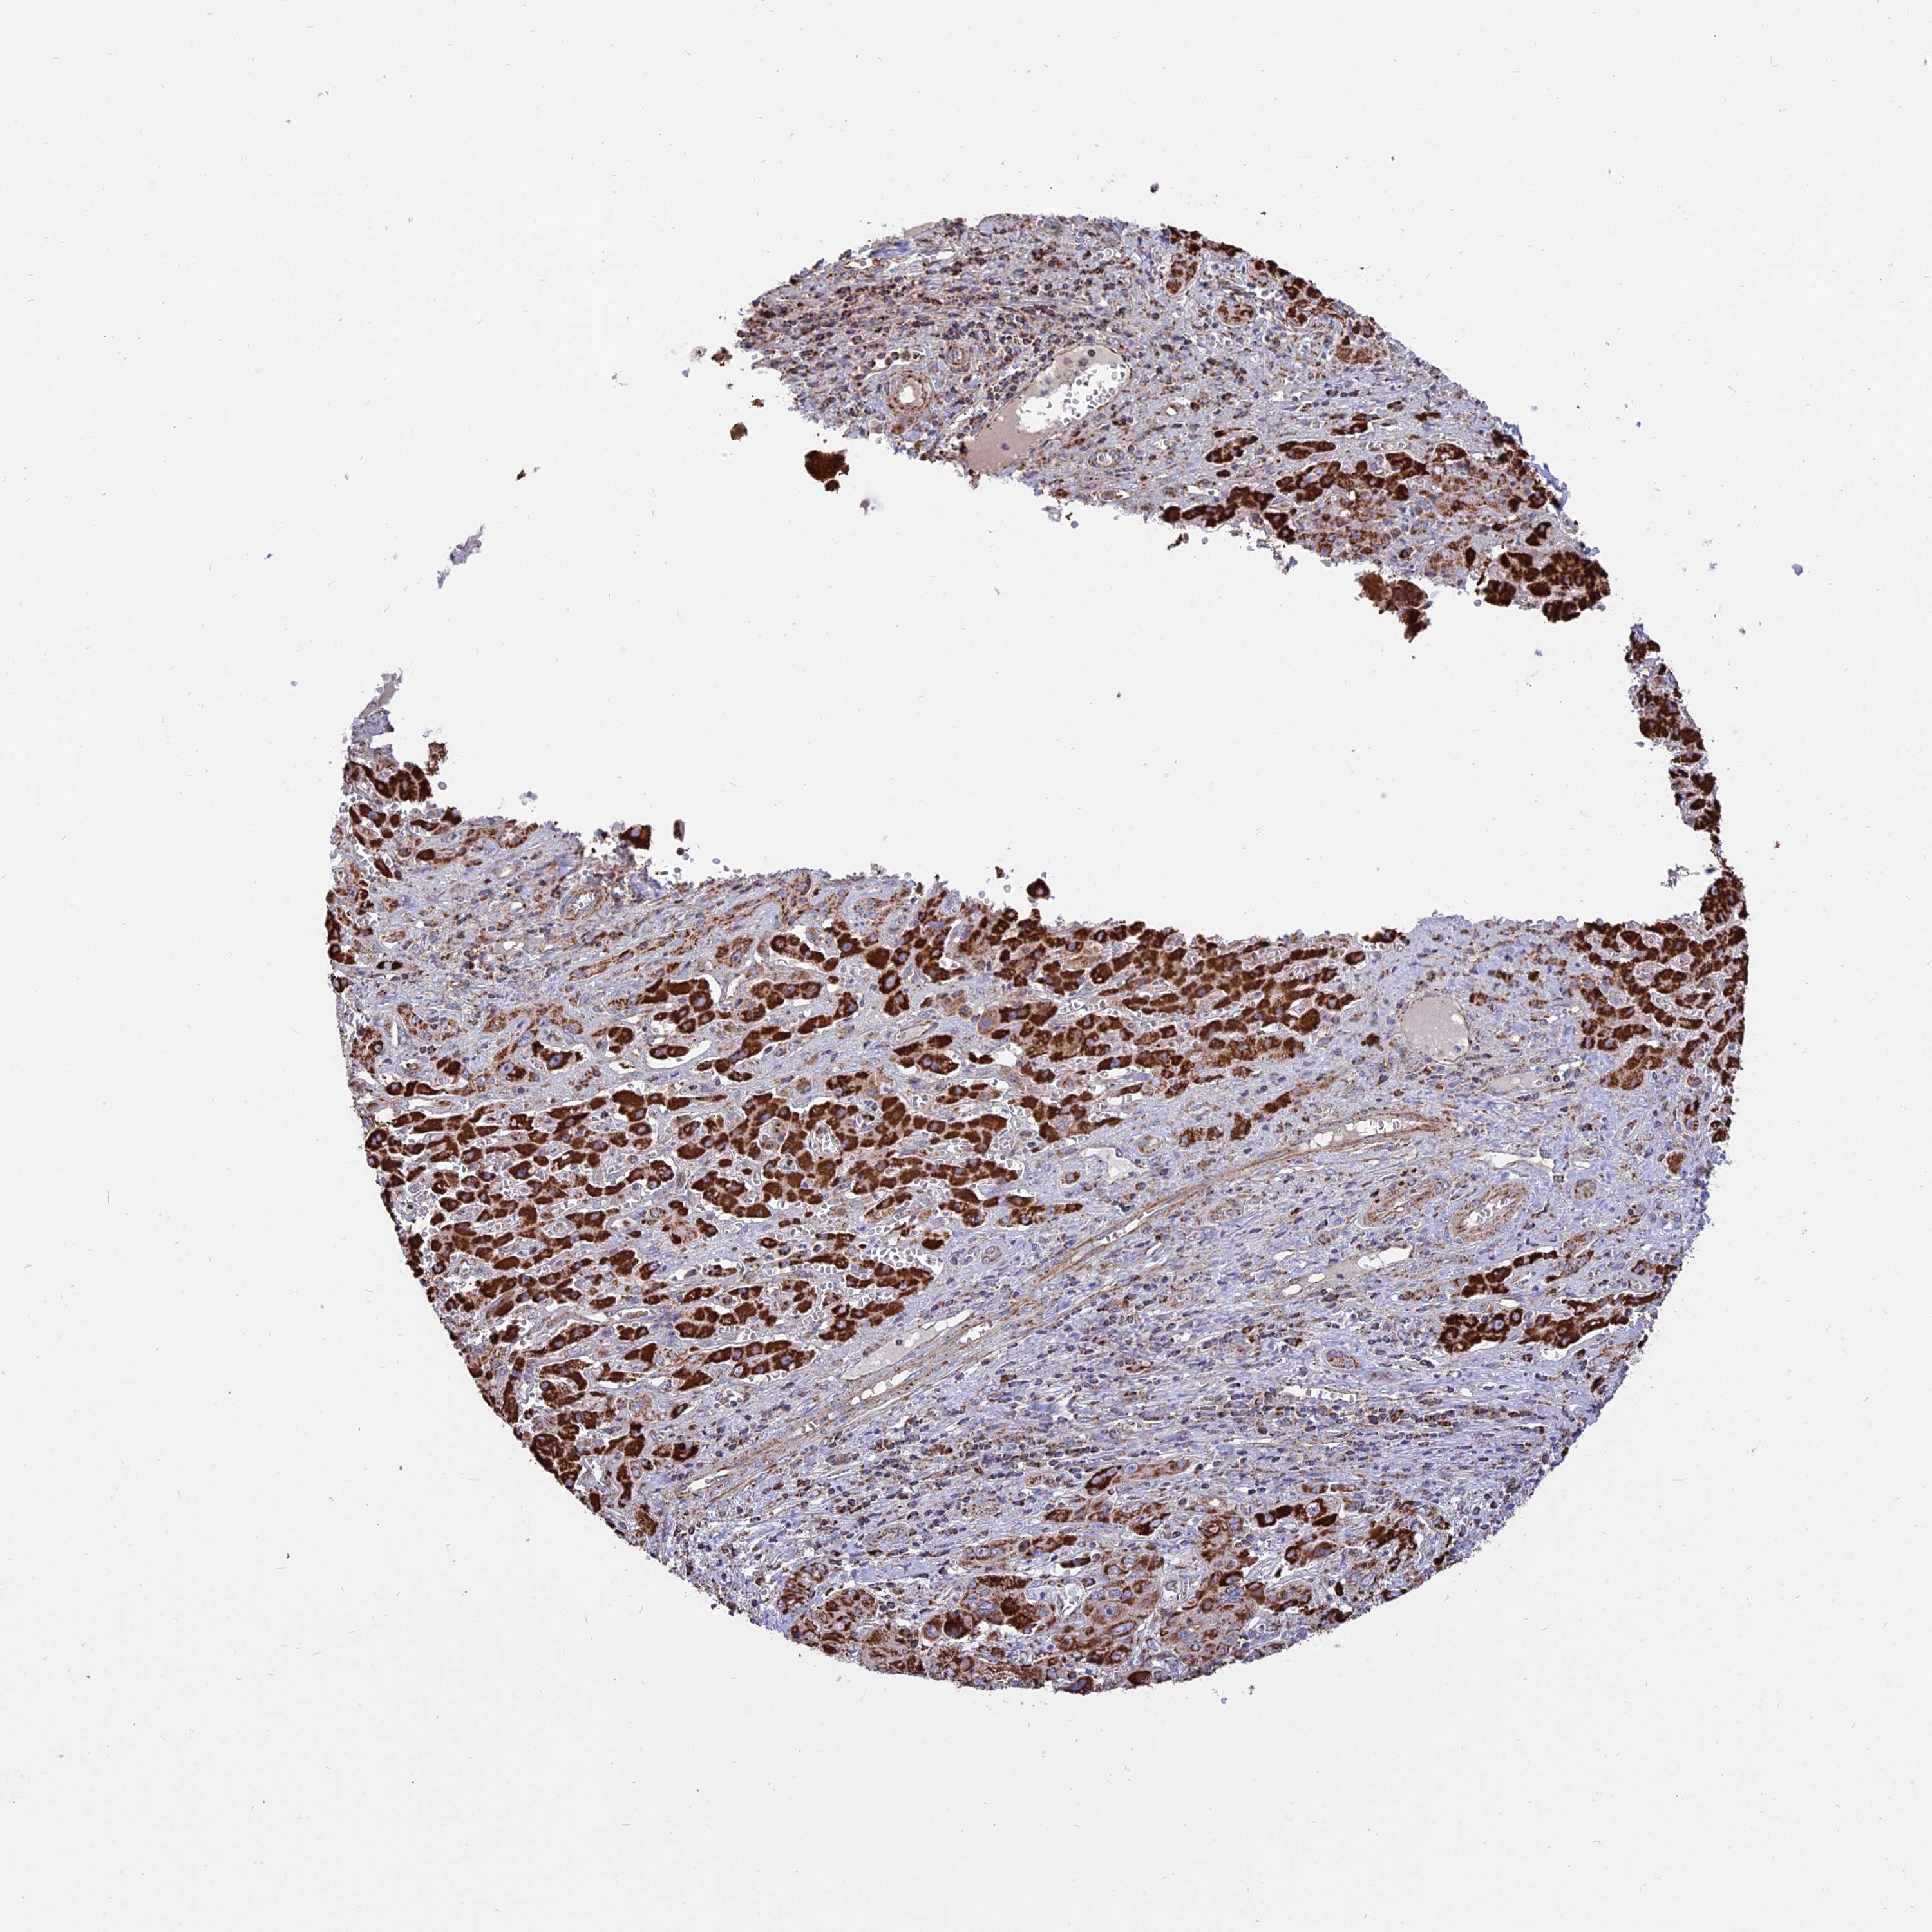

LIVER CANCER - Protein expressioni

A mouse-over function shows sample information and annotation data. Click on an image to view it in a full screen mode. Samples can be filtered based on level of antibody staining by selecting one or several of the following categories: high, medium, low and not detected. The assay and annotation is described here.

Note that samples used for immunohistochemistry by the Human Protein Atlas do not correspond to samples in the TCGA dataset.

Antibody stainingi

Antibody staining in the annotated cell types in the current human tissue is reported as not detected, low, medium, or high, based on conventional immunohistochemistry profiling in selected tissues. This score is based on the combination of the staining intensity and fraction of stained cells.

Each image is clickable and will lead to virtual microscopy that enables deeper exploration of all samples and also displays staining intensity scores, fraction scores and subcellular localization as well as patient and tissue information for each sample.

Antibody HPA041608

Antibody HPA042459

Staining

High

Medium

Low

Not detected

Intensity

Strong

Moderate

Weak

Negative

Quantity

>75%

75%-25%

<25%

None

Location

Nuclear

Cytoplasmic/membranous

Cytoplasmic/membranous,nuclear

Cholangiocarcinoma

Carcinoma, Hepatocellular, NOS